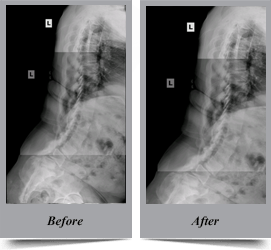

Congenital Scoliosis

Congenital scoliosis is the lateral curvature of spine that occurs in children